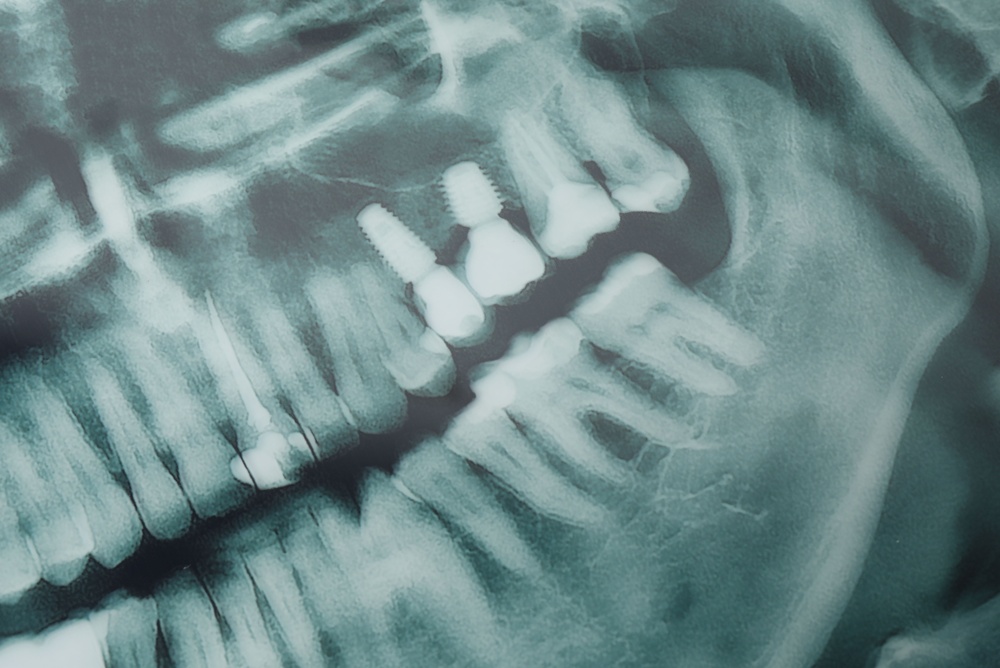

Your dentist will take X-rays or a CBCT scan, review your health, and create a treatment plan. This visit sets the timeline and shows whether grafting or extractions are needed first.

During implant surgery, the post is placed into the jaw. Healing takes weeks to months while bone grows around the implant — a process called osseointegration. Temporary restorations can be used for function and appearance during this time.